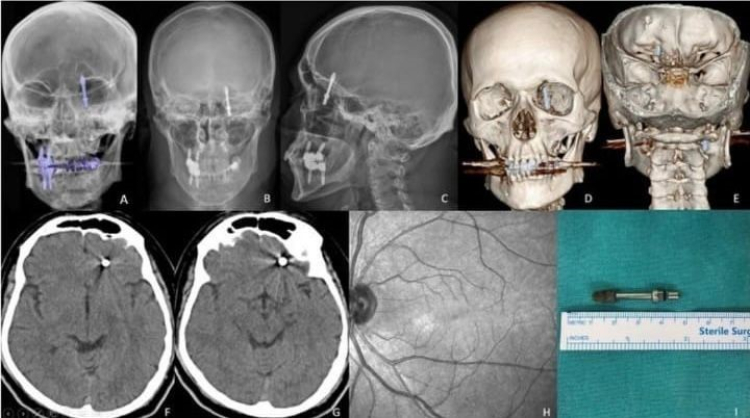

Bursa'da diş tedavisi için gittiği özel klinikte yaptırdığı implant işlemi, fabrika işçisi Ramazan Yılmaz'ın (40) hayatını kabusa çevirdi.

İddiaya göre, doktorun hatalı müdahalesi sonucu implant vidası çene kemiğini delip kafatasına saplandı. Ölümle burun buruna gelen talihsiz adam, saatler süren ameliyatla hayata tutundu. Ancak aradan geçen 2 yıla rağmen ne adalet yerini buldu, ne de sorumlular cezalandırıldı. Hatalı bulunan diş hekimine ise sadece 10 muayene ücreti ceza verildi.

Nilüfer ilçesinde özel bir diş kliniğinde muayene olan Yılmaz'a, dişlerinin sallandığı gerekçesiyle implant tedavisi önerildi. Ancak iddiaya göre, doktor A.D.'nin hatalı müdahalesi sonucu implant vidası çene kemiğini delip kafatasına saplandı.

Baygınlık geçiren Yılmaz, kliniğin kendi aracıyla hastaneye kaldırıldı. Tomografi çekiminde vidanın beynine kadar ilerlediği ortaya çıktı. Acil ameliyata alınan talihsiz adam, saatler süren operasyonla ölümden döndü.